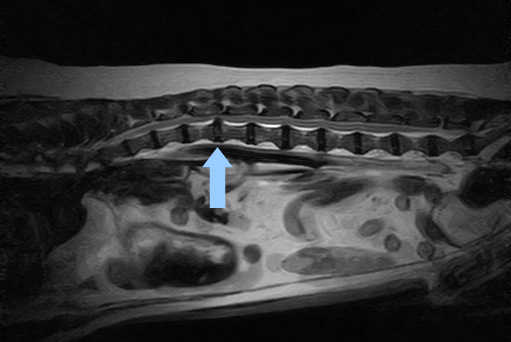

症例③ 胸腰部椎間板ヘルニア

急に後肢が立てなくなったため来院

| レントゲン検査 | 胸腰椎椎間板の石灰化 |

| 胸腰部MRI検査 | 重度の椎間板逸脱がみとめられた |

| 診断 | 胸腰椎椎間板ヘルニア(グレードⅢ) |

| 治療 | 外科的治療、リハビリテーション |

![]() 胸腰椎MRI検査(縦断面) |